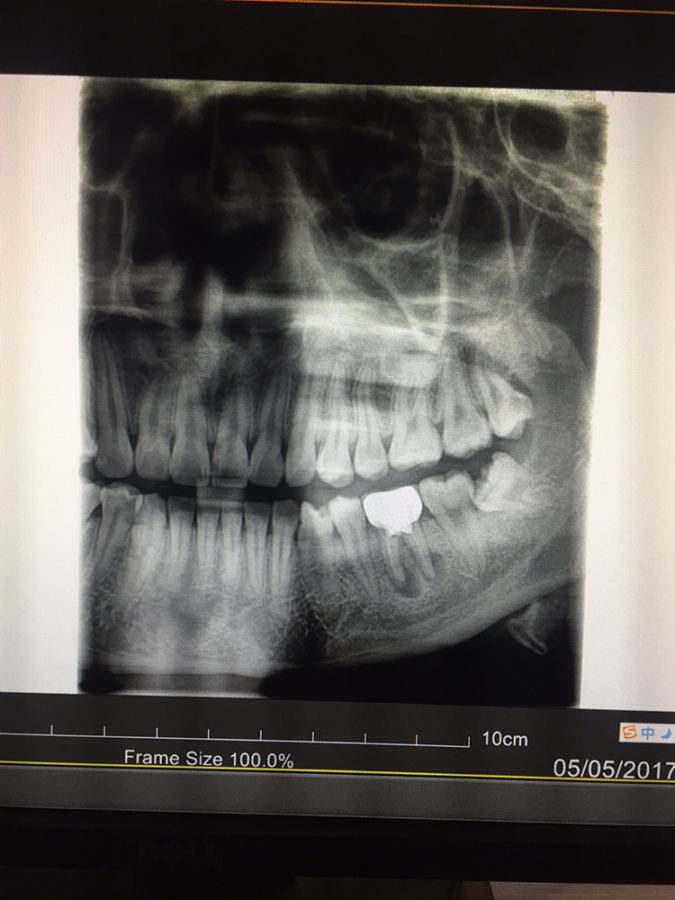

您好,我的左下第六颗牙齿约在两年前做了根管治疗并带上牙冠,一直相安无事。这两天突然开始疼痛,做了牙片后发现牙根尖处发炎严重,医生说根管再治疗难度高成功率也低,可以考虑拔牙,请问我该如何抉择呢?期待各位大神的回复,谢谢! @carci 发自小木虫IOS客户端 |